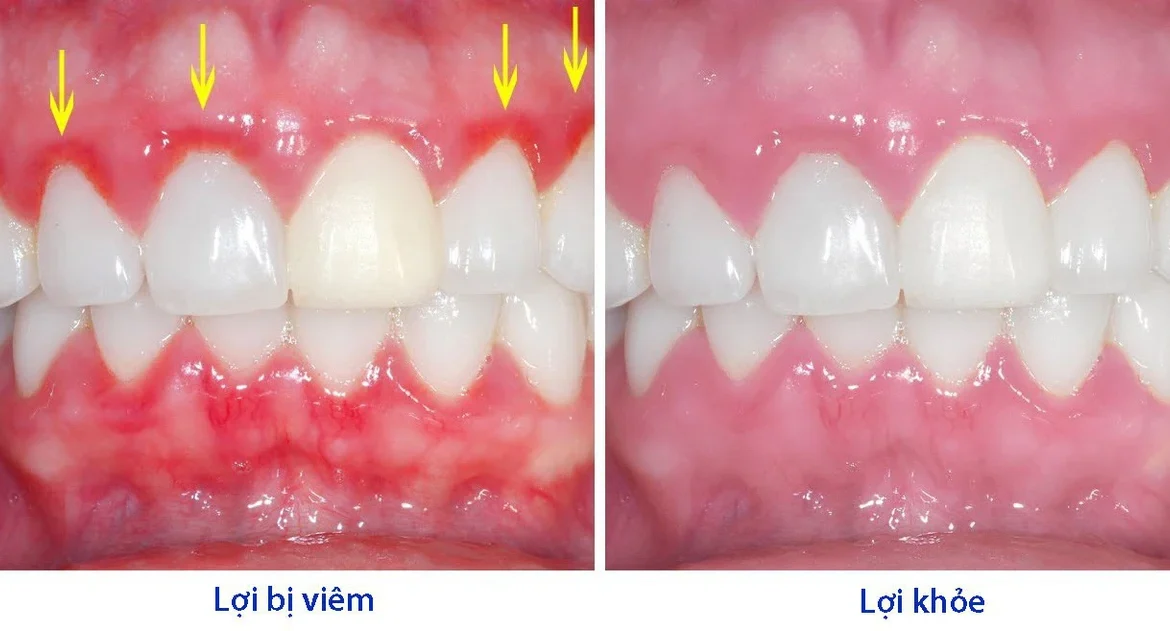

Viêm lợi răng hàm không phải là hiện tượng hiếm gặp. Người lớn và người cao tuổi có nguy cơ cao hơn do thói quen ăn uống,

nú răng bị chảy máu là một triệu chứng phổ biến mà nhiều người gặp phải trong sinh hoạt hàng ngày, đặc biệt khi đánh răng hoặc

Sưng lợi là tình trạng phổ biến mà nhiều người gặp phải trong cuộc sống hàng ngày. Đây không chỉ gây đau nhức và khó chịu mà

Tình trạng bị sưng lợi chân răng không còn xa lạ với nhiều người, từ trẻ em đến người lớn. Mặc dù đôi khi chỉ là một

Nướu sưng (hay còn gọi là sưng lợi) là một tình trạng răng miệng khá phổ biến, gây ra không ít phiền toái và đau nhức cho